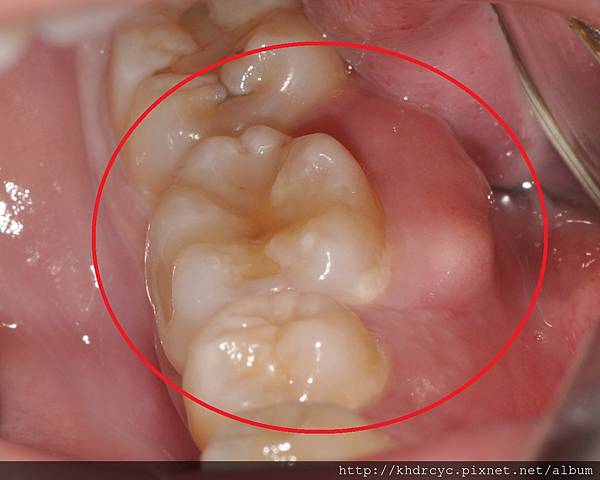

只要局部清潔洗牙

把膿包旁邊的牙結石 塞住的牙垢清掉

搭配膿包沖洗 三天左右就會消掉

消腫之後常可以明顯看到殘留的牙結石

若不改進清潔習慣 往往還會再發

所以若發生牙周膿腫 盡快請醫師治療

且後續要繼續牙周病治療

改善清潔習慣 善用牙刷牙線漱口水

定期回診洗牙 才不會反覆發作

最後變成嚴重的牙周病